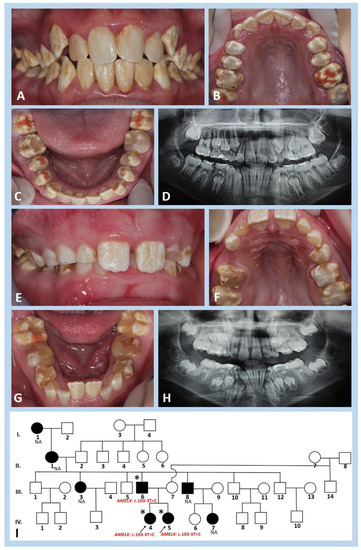

3.1. Clinical and Radiographic Findings

| Number | Family (F) | Gender | Predicted Mode of Inheritance | Phenotype * | |

|---|---|---|---|---|---|

| Hypomineralisation Type | Hypoplastic Type | ||||

| 1 | F1 | Female | ** | + | |

| 2 | F2 | Female | ** | + | |

| 3 | F3 | Male | AD | + | |

| 4 | Male | + | |||

| 5 | F4 | Male | AD | + | |

| 6 | Female | + | |||

| 7 | Female | + | |||

| 8 | Male | + | |||

| 9 | F5 | Female | ** | + | |

| 10 | F6 | Female | ** | + | |

| 11 | F7 | Female | AD | + | |

| 12 | Male | + | |||

| 13 | F8 | Male | AD | + | |

| 14 | Female | + | |||

| 15 | F9 | Female | AD | + | |

| 16 | F10 | Female | ** | + | |

| 17 | F11 | Female | AR | + | + |

| 18 | F12 | Male | AR | + | |

| 19 | F13 | Male | AD | + | + |

| 20 | Female | + | + | ||

| 21 | F14 | Female | AR | + | |

| 22 | F15 | Male | AD | + | + |

| 23 | F16 | Male | AD | + | + |

| 24 | Male | + | + | ||

| 25 | F17 | Female | AD | + | + |

| 26 | Male | + | + | ||

| 27 | F18 | Female | AR | + | |

| 28 | F19 | Female | ** | + | |

| 29 | F20 | Male | AD | + | |

| 30 | Male | + | |||

| 31 | F21 | Male | AD | + | |

| 32 | F22 | Female | ** | + | |

| 33 | F23 | Female | ** | + | |

| 34 | F24 | Male | AD | + | |

| 35 | Male | + | |||

| 36 | F25 | Female | X-linked | + | + |

| 37 | Female | + | + | ||

| 38 | F26 | Male | ** | + | |

| 39 | F27 | Female | X-linked | + | + |

| 40 | F28 | Female | ** | + | |